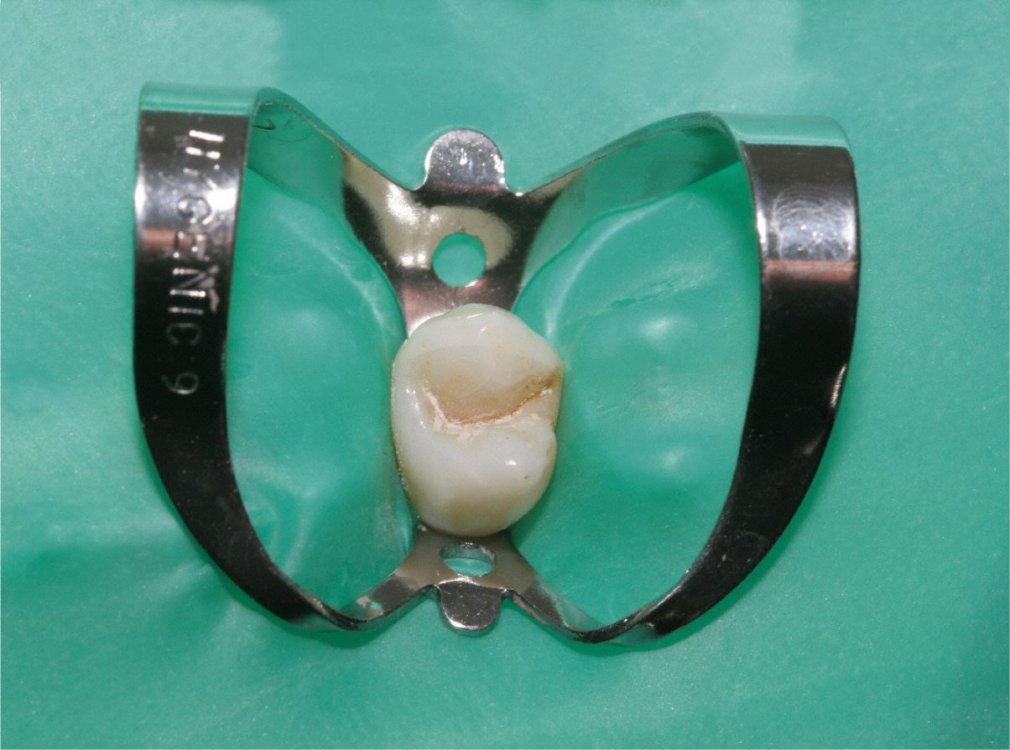

Kofferdam

Für eine effiziente Wurzelbehandlung müssen Bakterien restlos aus dem Wurzelkanal beseitigt werden.

Dafür benutzt man einen speziellen Spanngummi, genannt "Kofferdam", der sowohl den Zahn isoliert, als auch das Eindringen von Bakterien aus der Mundhöhle in den Zahn verhindert. Gleichzeitig wird vermieden, dass der Patient kleine Instrumente oder Materialien verschluckt.